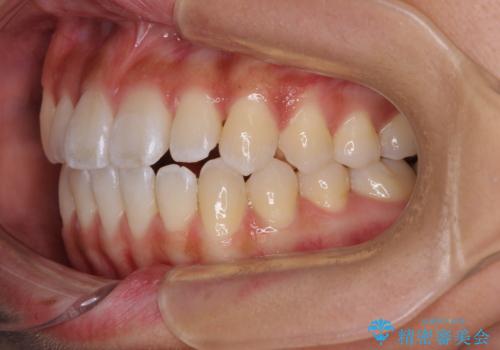

八重歯とオープンバイト 急速拡大装置を用いた矯正治療

- 前歯の開咬と、上顎前歯の八重歯やデコボコを気にして来院された患者様です。

急速拡大装置で上顎骨を十分に拡大できたことで、非抜歯で八重歯を歯列に納めることができました。

患者様はもちろん、我々もここまで綺麗に仕上げられるとは想像もできず、お互いに大変満足な治療となりました。